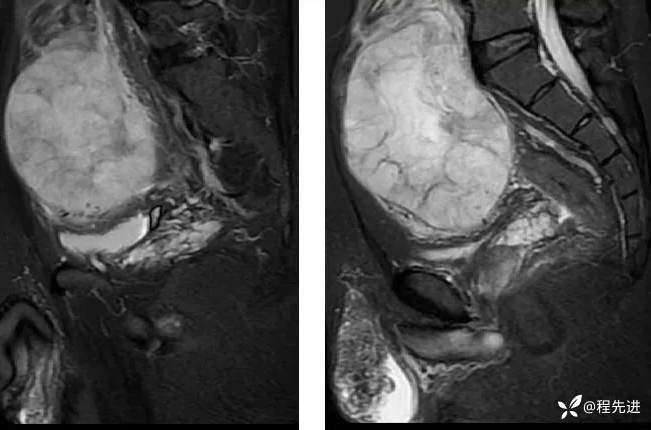

【腹盆】特别精彩病例|下腹痛20余天,男性病人腹腔巨大肿块该如何诊断

【患者信息】:男,41岁

【主诉】:下腹痛20余天

既往史:隐睾

肿瘤标志物:甲胎蛋白(AFP)>10000

增强: